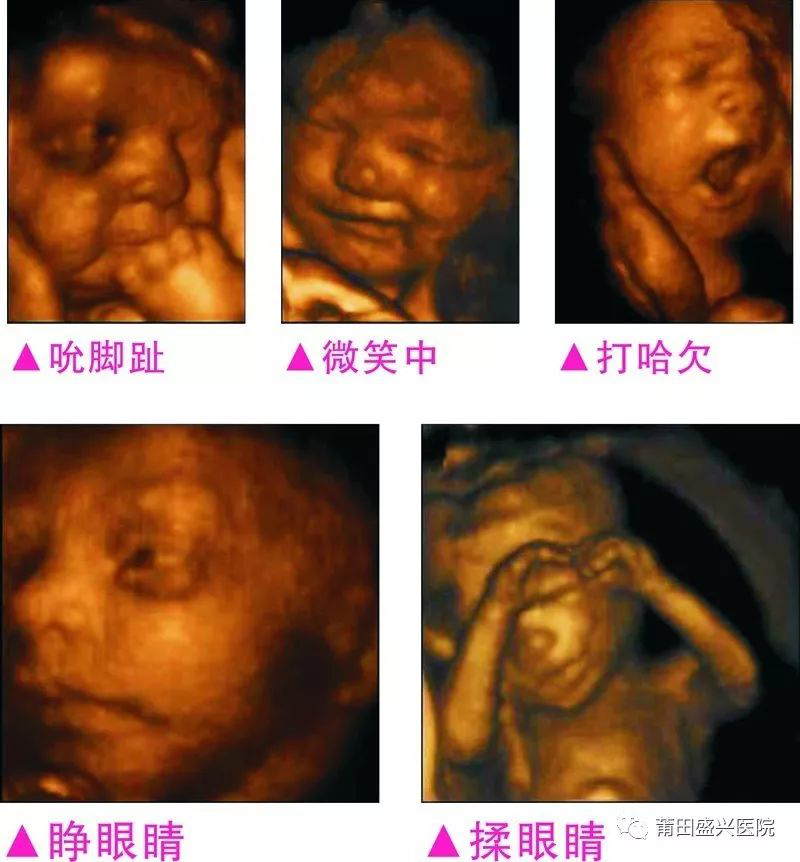

您一定不知道寶寶有多調(diào)皮可愛

你一定不知道寶寶這么小就有這么多表情

四維容積成像技術(shù),智能光源系統(tǒng)展現(xiàn)梯度亮度,渲染畫面,提高容積成像品質(zhì),高清顯示腹中寶寶的實(shí)時(shí)動(dòng)態(tài)影像,完整記錄寶寶的一舉一動(dòng),讓準(zhǔn)爸媽與寶寶Di一次幸福“見面”,更可刻錄成高清視頻,送給未來寶寶的珍貴禮物。